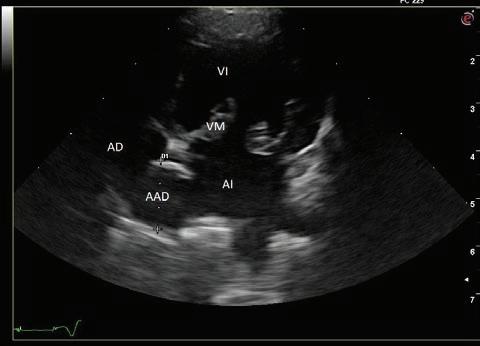

y a la condición corporal del paciente. En la proyección ventrodorsal, el mediastino craneal se observó en el límite superior de tamaño, presentándose un tamaño dos veces superior a la anchura de la vértebra torácica (Fig. 1). Este cambio es compatible con una imagen artefactual secundaria a la leve rotación que presenta la radiografía y a la condición corporal del paciente. El diagnóstico radiológico más probable fue una masa mediastínica craneoventral y cardiomegalia izquierda. En la ecocardiografía transtorácica se confirmó el diagnóstico de enfermedad degenerativa de la válvula

mitral (EDVM), presentando engrosamiento, prolapso e insuficiencia valvular, dilatación del atrio izquierdo (AI/AO=1,9) y leve aumento de las dimensiones diastólicas del ventrículo izquierdo normalizado al peso del paciente (NLVDD=1,7). Las presiones de llenado intracardiacas se estimaron como normales, ya que el flujo transmitral presentó un patrón de relajación anómala y la velocidad pico de E fue de 0,8 m/s. En función de estos hallazgos se confirmó el diagnóstico de enfermedad degenerativa valvular mitral con cardiomegalia izquierda y sin hallazgos compatibles con insuficiencia cardiaca congestiva, por lo tanto en estadio ACVIM B2. En las vistas ecocardiográficas paraesternal derecha de 4 cámaras y apical izquierda de 4 cámaras se visualizó una estructura redondeada y anecógena de 15 mm, con flujo sanguíneo en Doppler color, adyacente al corazón (Fig. 2). Este hallazgo es compatible con dilatación aneurismática de las estructuras vasculares o las cavidades cardiacas, si bien no

Figura 2. Ecocardiografía. (A) Vista apical izquierda de 4 cámaras optimizada para ADD. Engrosamiento de la válvula mitral (VM), dilatación moderada de atrio izquierdo (AI) y ventrículo izquierdo (VI). Estructura redondeada y anecógena de 15 mm con flujo sanguíneo (AAD), adyacente al corazón. AD: atrio derecho. (B) Vista paraesternal derecha de 4 cámaras optimizada para el atrio izquierdo. Estructura redondeada y anecógena (AAD) asociada al corazón. AD: atrio derecho.